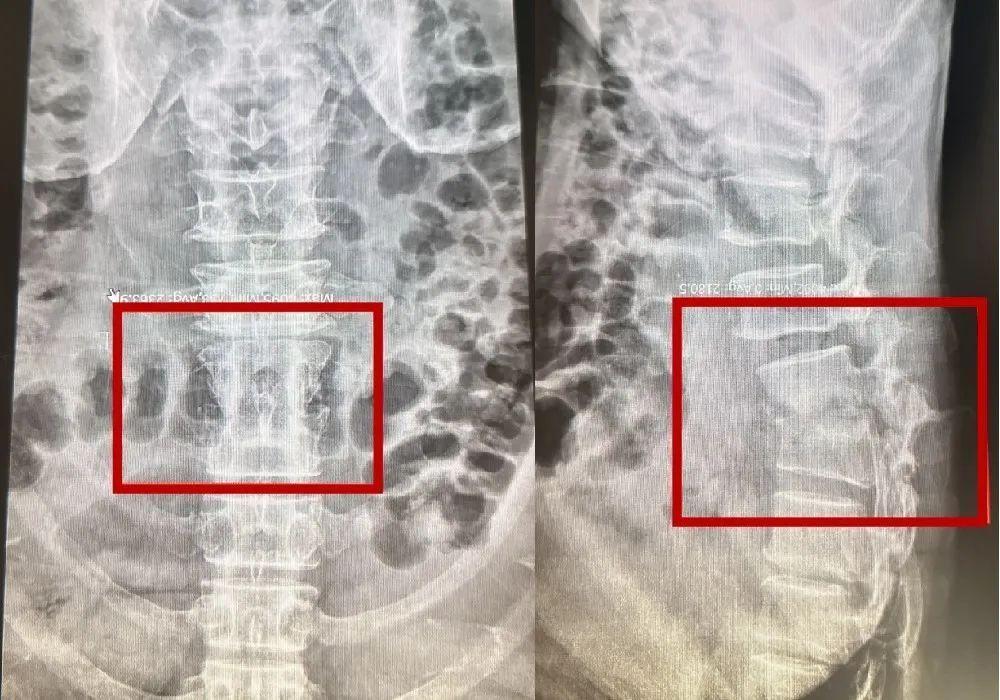

术前,检查显示刘先生腰骶1、2椎体病灶

随后,经在佛山顺德打工的老乡推荐,刘先生辗转来到了顺德和平外科医院就医。经详细检查,化验及影像结果揭示了“真相”——其腰骶1、2椎体出现破坏性病灶,结核杆菌侵蚀骨骼并压迫神经,导致疼痛和驼背畸形。“这是典型的脊柱结核表现,需立即干预。”该院负责人称。

手术中,团队彻底清除病灶区域坏死组织,采用植骨融合技术重建脊柱稳定性,并植入8枚钢钉矫正畸形。院方介绍称,结核破坏的椎体就像被虫蛀的木头,必须清除“朽木”并用自体骨填充,再以内固定器械“加固”,才能恢复脊柱承重功能。术后次日,刘先生即感疼痛大幅缓解,佩戴支具后已可下床活动。当下床瞬间,他如释重负,终于能昂首挺胸走路了。